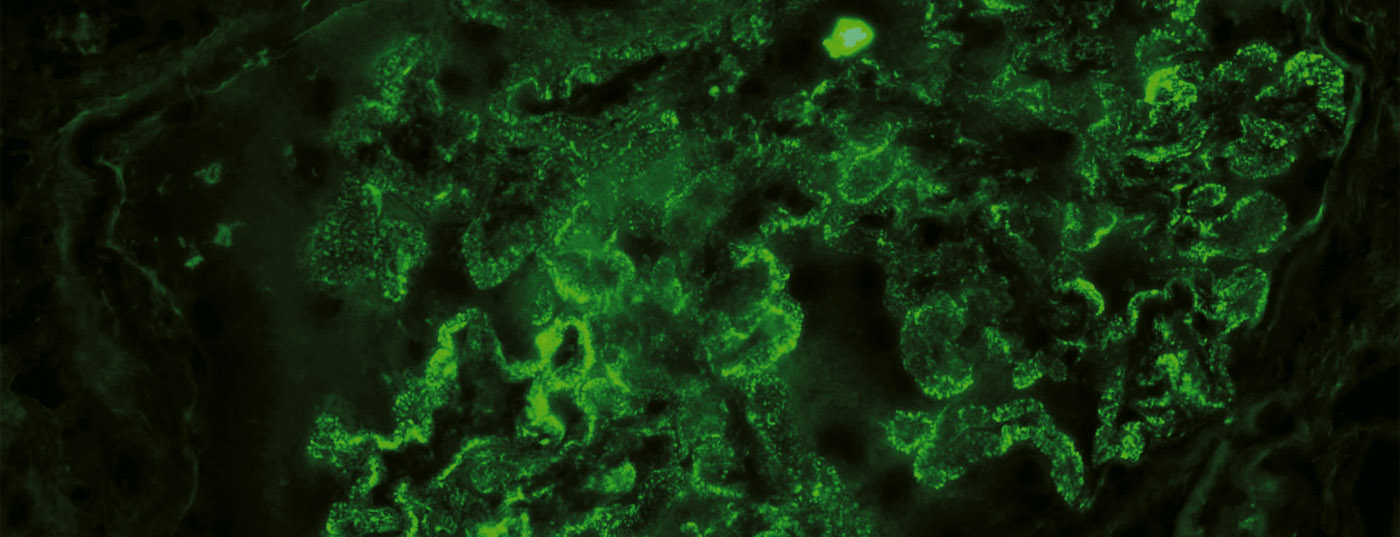

glomerulum

Neue Behandlungsmöglichkeiten bei glomerulären Erkrankungen

Glomeruläre Erkrankungen sind wichtige Ursachen für ein ­terminales Nierenversagen. Pathogenetisch stehen immun­vermittelte Prozesse im Vordergrund. Dank fortschreitender Erkenntnisse über die Pathophysiologie und moderner gentechnischer Methoden besteht die Hoffnung auf eine möglichst gezielte und nebenwirkungsarme Therapie. Neue Behandlungsansätze glomerulärer Erkrankungen werden in diesem Artikel kurz ­beleuchtet und einige Substanzen exemplarisch vorgestellt.